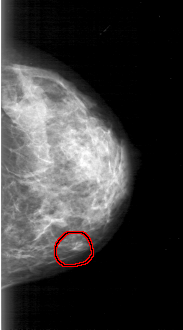

D_4031_1.RIGHT_MLO

RIGHT_MLO LINES 5176 PIXELS_PER_LINE 3001 BITS_PER_PIXEL 12 RESOLUTION 43.5 OVERLAY

FILE: D_4031_1.RIGHT_MLO.OVERLAY

TOTAL_ABNORMALITIES 1

ABNORMALITY 1

LESION_TYPE MASS SHAPE OVAL MARGINS OBSCURED

ASSESSMENT 0

SUBTLETY 5

PATHOLOGY BENIGN

TOTAL_OUTLINES 1

BOUNDARY